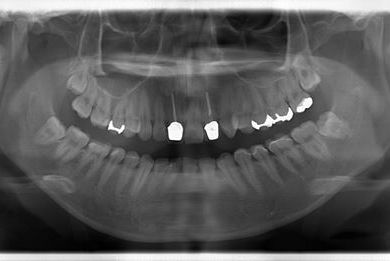

| 性別/年齢 | 女性 / 21歳 | ||||||||||||||||||||||||||||||||

| 主訴 | 現在、金属の入っている歯が虫歯になっているようなので、治してセラミックにしたい。 | ||||||||||||||||||||||||||||||||

| 治療方針 | セラミック治療にて審美的回復を行う。 | ||||||||||||||||||||||||||||||||

| 治療内容 | ハイブリッドセラミックインレー6本 | ||||||||||||||||||||||||||||||||

| 総治療費 | 189,000円 | ||||||||||||||||||||||||||||||||

| 治療期間 | 3ヶ月 |